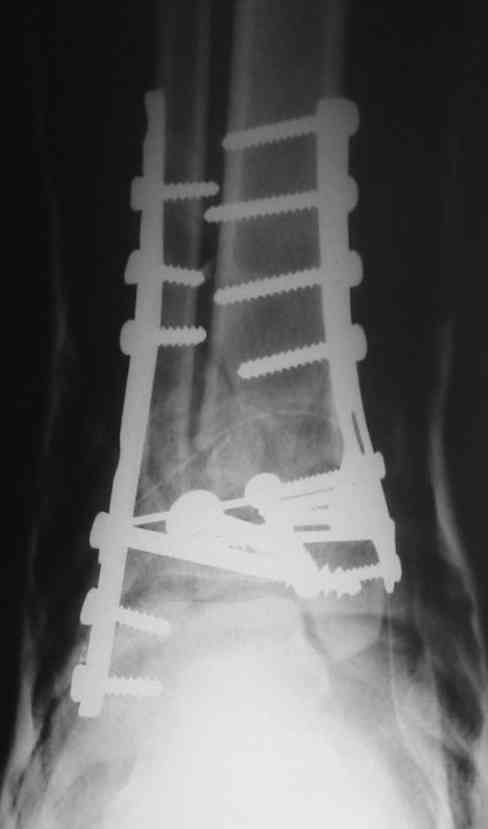

Это типичный перелом пилона, который надп лечить только открыто.Извини те что опоздал к обсуждению, но даже если вы уже оперировали больного по Илизарову это даже лучше.Посылаю картинки.

Посмотрим вроде прошло если понравится напишите расскажу как это сделать.По принципам АО кстати при поступлении сначала восстанавливают длину малоберцовой кости фиксируют пластиной 1/3 трубки потом накладывают аппарат наружной фиксации и через 7-10 дней открыто восстанавливают большеберцовую кость.С уважением Дрягин

На рентгенограммах типичный перелом пилона по типу С-3. есть опыт до 100 открытых опреаций у нас в клинике. 20 примерно в год. Принцип один -все внутрисуставные переломы нуждаются в открытой репозиции и внутренней стабильной фиксации. При поступлении КТ не надо, так как получается только нагромождение костей. Истинной картины нет. Главное восстановить длину малоберцовой кости - это ключ к успеху. При поступлении меньше всего надо думать о сосудистых расстройствах, т.к. сама операция и репозиция даже сначала частичная даёт улучшение сосудитых нарушений. Причём очень быстро. Операция в 2этапа. При поступлении доступ позади наружной лодыжки, причём обязательно. После этого репозиция малоберцовой кости и фиксация пластиной 1/3 трубки под винт 3,5. Дренаж и любой аппарат наружной фиксации. Затем после спадения отёка на 5-7-10 день аппрат снимается и дугообразный разрез спереди от медиальной лодыжки 10-12 см. Главной чтобы расстояние между 1 и вторым разрезом было не меньше 7-8 см. Тогда не будет некрозов лоскутов. Таранная кость используется как матрица на неё укладываются отломки и фиксируются пицами. Ренг-контроль. Отломки лежат все отдельно, но ничего не высыпется. При переломах С-3 всегда нужна костная пластика (из крыла). Фиксация пластиной лист клевера простой или LCP. Гипс не нужен. Дренаж до 48 часов. Операция длится 3-4 часа обязательно без жгута. Посылаю примерно такой же случай.